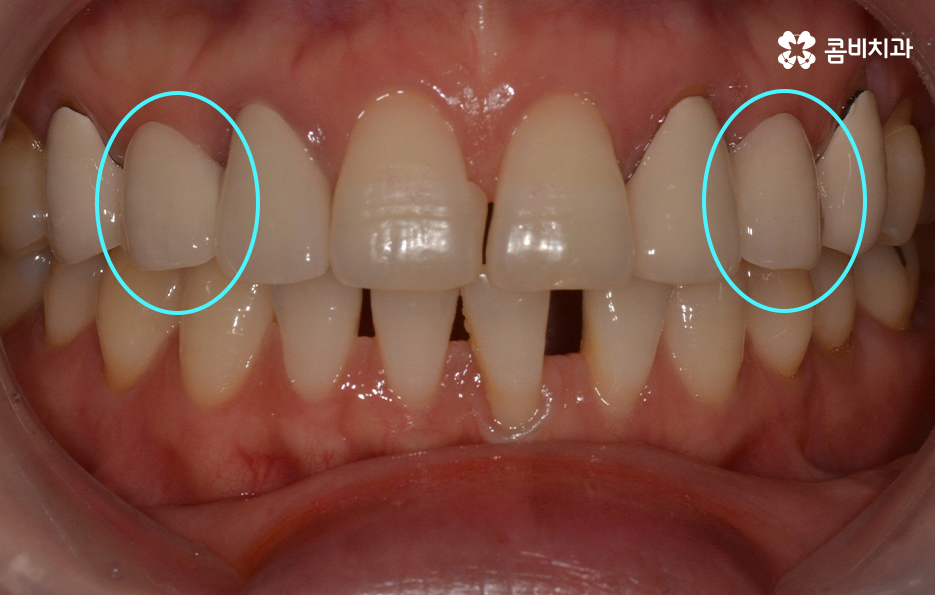

위에 표시된 치아는 이미 발치가 된 상태에서 임시치아를

부착하고 생활을 하셨던 환자이며 고르지 못한 치열을

개선하고 임시치아를 부착한 치아에 임플란트를 식립한 사례라고 할 수 있어요.

자세히 보시면 임시치아라는 것을 알 수 있고 엑스레이

사진을 보면 더 자세히 알 수 있습니다.